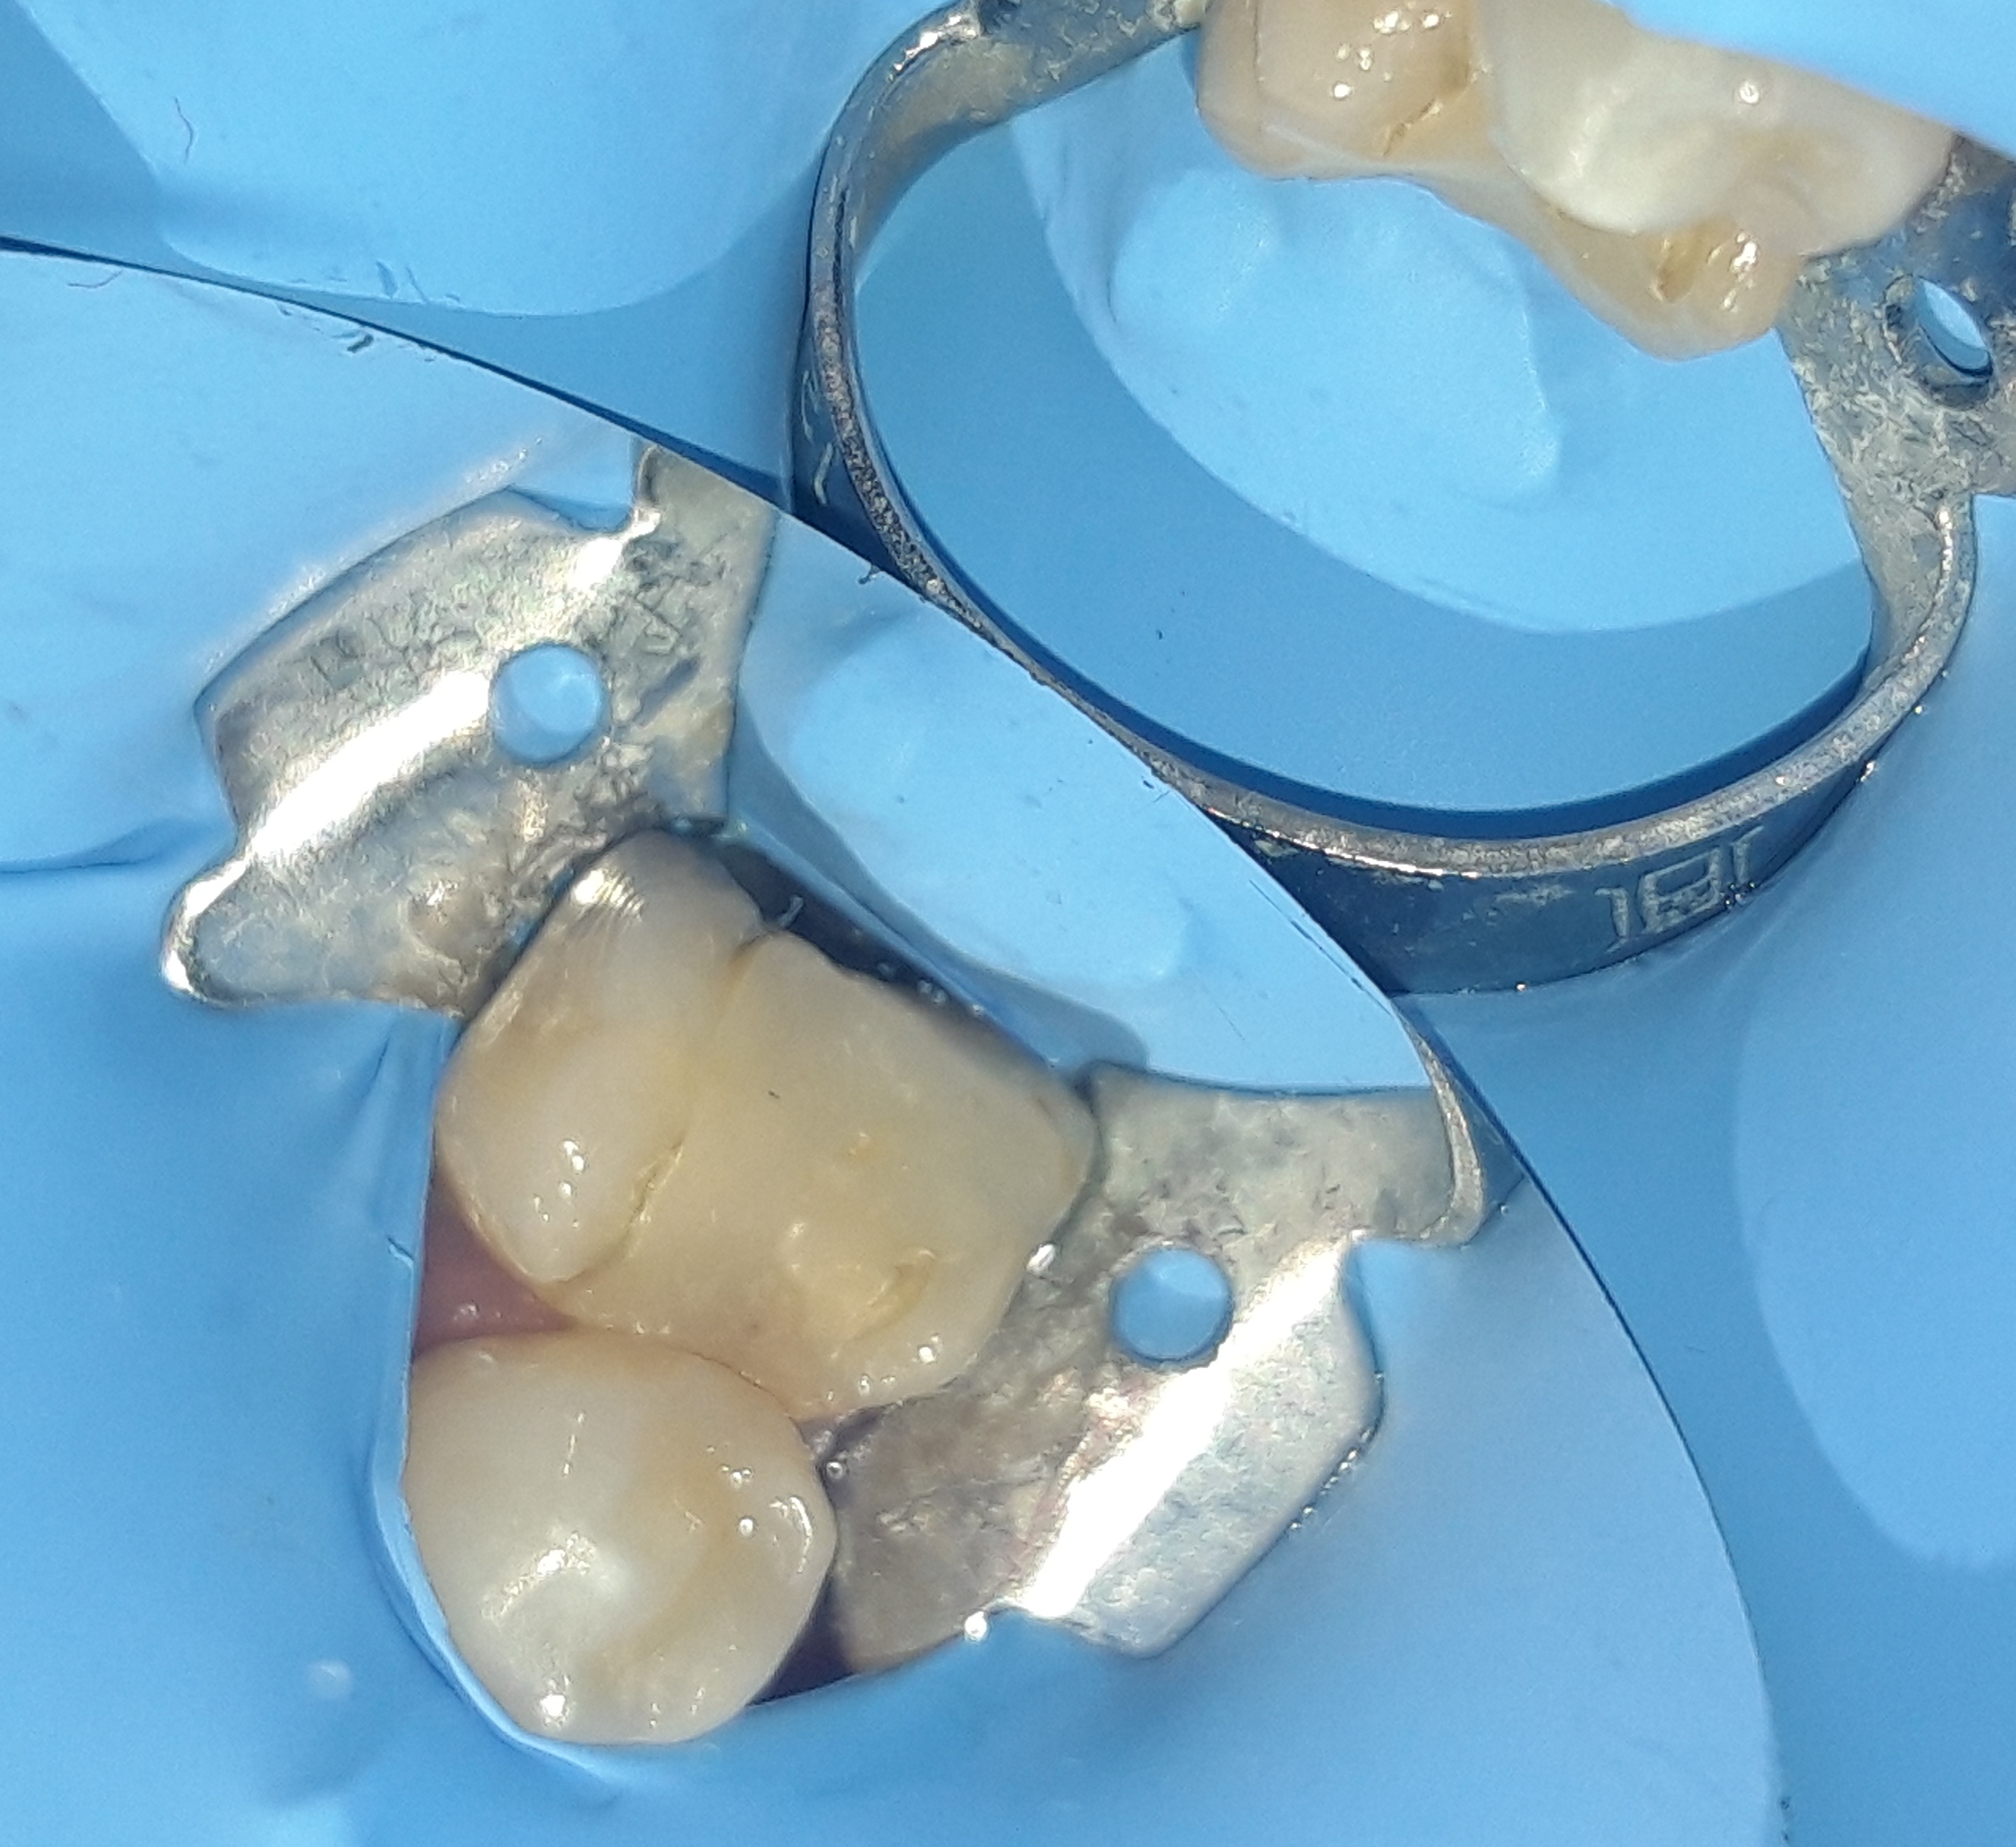

Εικόνα του δοντιού πριν τη λήψη αποτυπώματος

Κλινική εικόνα του δοντιού μετά τον εκτροχισμό του